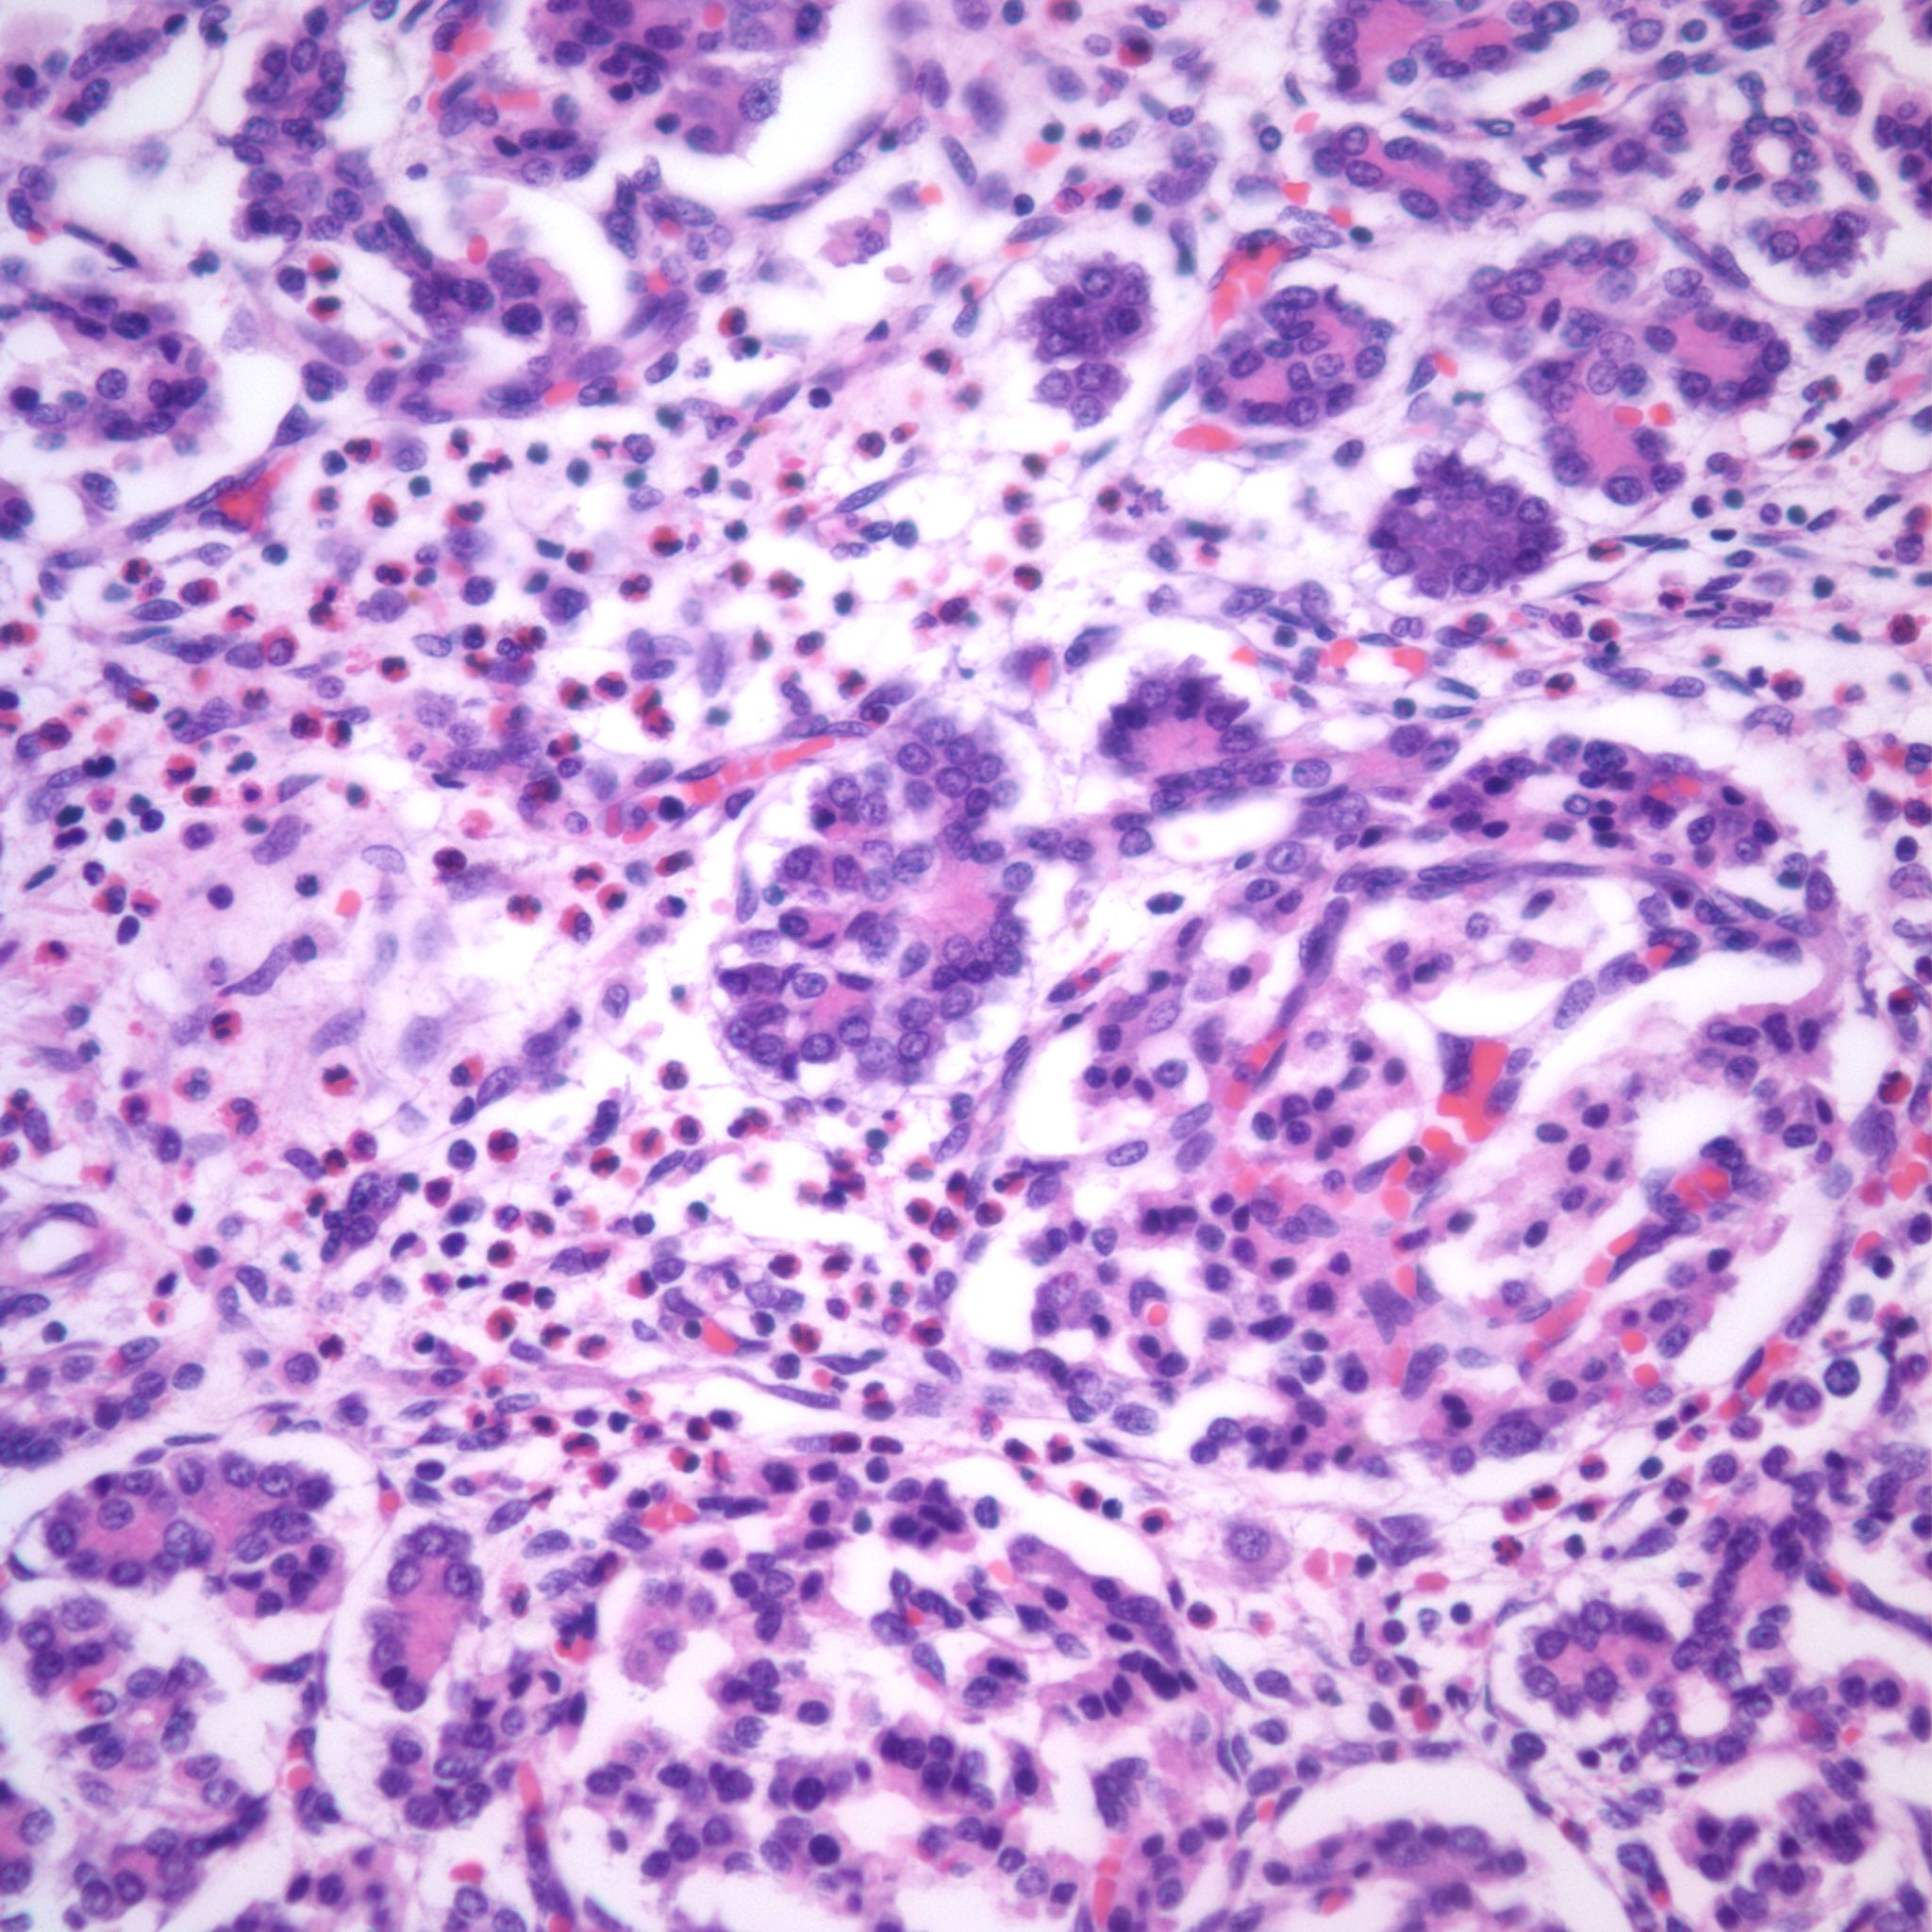

With islet hypertrophy, there is sometimes an infiltrate of predominantly eosinophils in the islet[18, 19]. Van Assche has asserted that this is evidence of type I diabetes in the mother [9]. Based on models of autoimmune diabetes, the possibility exists that the eosinophils are reducing the number of insulin cells, even as those cells must functionally increase. In a mouse model of immune diabetes, alpha islet cells (glucagon producing) were decreased in the adult mice consistent with damage to islet cells[20]. Eosinophils in the islets are also seen in pancreases with non-diabetic associations with islet hyperplasia, such as the Noonan phenotype described above (Fig 23).